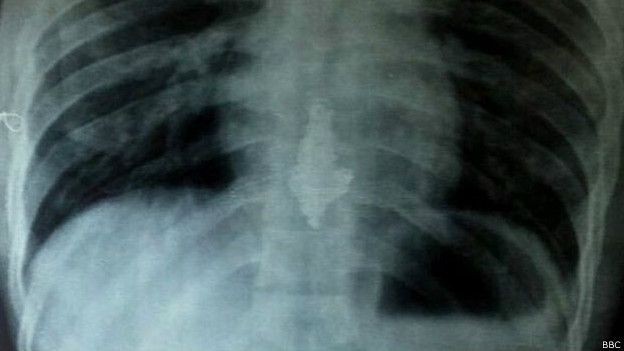

Yadav fue sometido a la dieta después de que las radiografías que se le tomaron mostraron la joya alojada en el esófago.

Yavad fue trasladado a un hospital y sometido a una radiografía que reveló el collar dentro de su cuerpo.